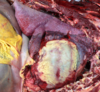

Q

This is a liver. What lesion is shown here?

A

multifocal hepatic abscesses